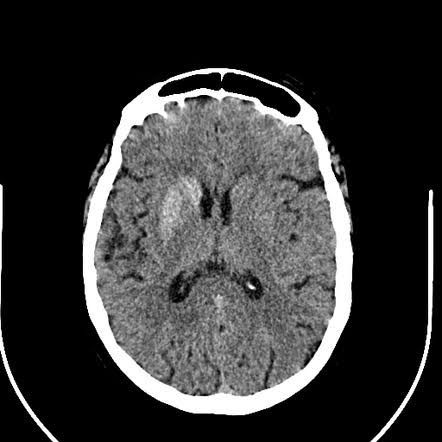

Hemiballismus is a hyperkinetic involuntary movement disorder characterized by intermittent, sudden, violent, involuntary, flinging, or ballistic high amplitude movements involving the ipsilateral arm and leg caused dysfunction in the central nervous system of the contralateral side.